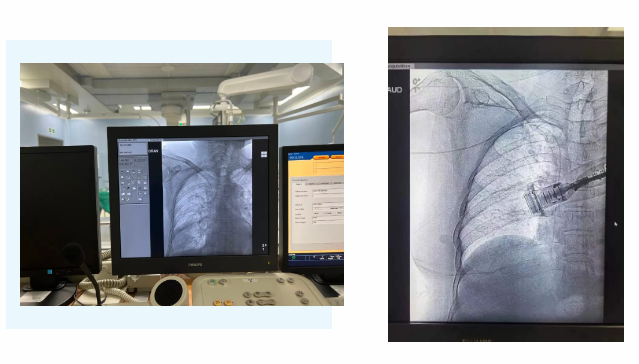

在麻醉手術(shù)中心的配合下,手術(shù)首先由韓海靜護(hù)士長(zhǎng)在超聲引導(dǎo)下應(yīng)用“塞丁格”法穿刺將針尖一樣細(xì)的導(dǎo)絲送入血管,術(shù)中在DSA透視下將導(dǎo)管沿著血管送達(dá)上腔靜脈,尖端精準(zhǔn)定位至上腔靜脈開口處。隨后,胸腔外科支亞男主治醫(yī)師在穿刺點(diǎn)下方取2厘米小切口內(nèi)進(jìn)行上臂港囊袋和隧道的制作及導(dǎo)管與港座連接,最后進(jìn)行港體埋植及皮內(nèi)縫合,使患者切口隱蔽美觀創(chuàng)傷小,術(shù)中出血量極少。手術(shù)在X片影像留影,最終手術(shù)順利完成。